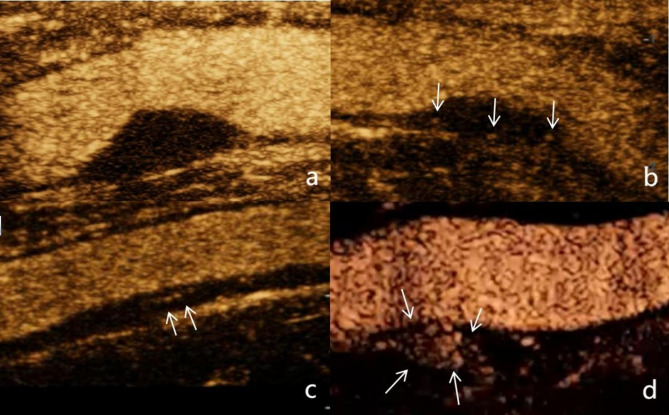

易损斑块是急性缺血性事件的重要危险因素,斑块内新生血管(IPN)是评价斑块易损的重要指标。本文综述了IPN在评估颈动脉斑块易损性中的重要性、IPN超声检查的现状以及IPN超声成像技术的进展,包括:高超的微血管成像技术;对比度增强超声;平面波超灵敏血流成像;超声靶向微泡破坏;超声超分辨率成像。旨在为缺血性心脑血管事件的预防和治疗提供参考。

Vulnerable plaques are significant risk factors for acute ischemic events, and intraplaque neovascularization (IPN) is an important indicator for evaluating plaque vulnerability. This review summarizes the importance of IPN in the assessment of carotid plaque vulnerability, the current status of ultrasound examination of IPN, and the technical advancements in ultrasound imaging of IPN, These techniques include: Superb micro-vascular imaging; Contrast-enhanced ultrasound; Plane wave ultra-sensitive blood flow imaging; Ultrasound-targeted microbubble destruction; Ultrasound Super-Resolution Imaging. Aiming to provide a reference for the prevention and treatment of ischemic cardiovascular and cerebrovascular events.